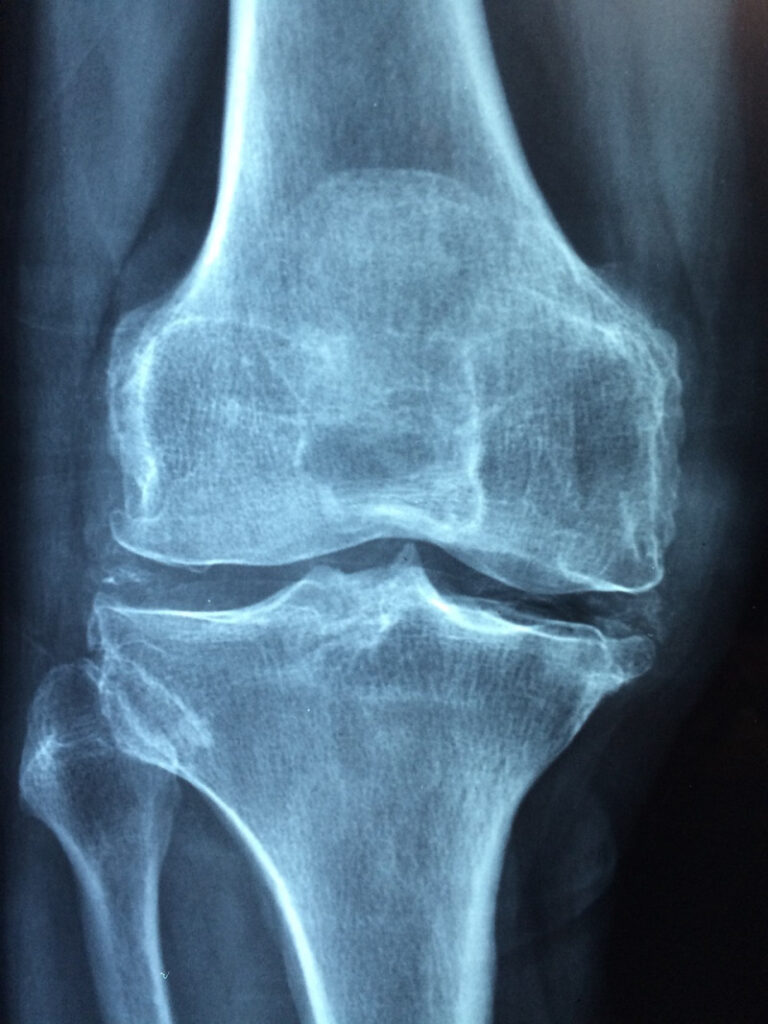

Joint pain, particularly in the knees, shoulders, hips, and elbows, is often caused by degenerative conditions like osteoarthritis or by acute injuries. PRP therapy can be effective in treating these conditions by reducing inflammation and promoting the repair of damaged cartilage.